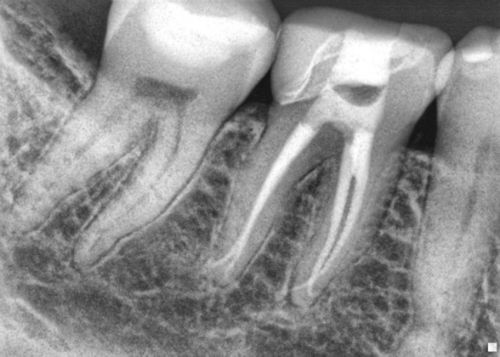

With the information from the scan I was able to determine exactly how far I needed to progress in order to find each canal. I could also confirm, in three dimensions, that I was centered within the mesial buccal canal path and “on target” to find the canal. CBCT technology is an incredible innovation for the field of endodontics. We are finding that a three dimensional rendering can elevate the degree of care not only with pre-operative diagnostics but also with intera-operative treatment. The final radiograph can be seen below with four separate portals of exit for the four canals. Stay tuned for more blogs on the use of CBCT in endodontics.

Post Operative Radiograph